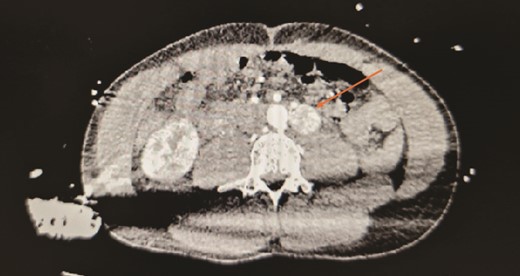

A 30-year-old urology registrar presented to the emergency department complaining of headache, nausea and abdominal pain, and was found to be hypertensive. He became very agitated whilst on the ward and was intubated. A computed tomography (CT) of the brain was normal, but subsequent CT of his abdomen and pelvis revealed a 2 × 2 × 3 cm hypervascular mass adjacent to his aorta just above the bifurcation. Initially suspected to be an aneurysm, it was later identified as a paraganglioma (Figs 1 and 2). He was then referred to the endocrine surgery team.

Contrasted CT in arterial phase, in the axial plane, showed a contrast enhanced, hyperdense, heterogenous lesion located over the left para-aortic region, measuring ⁓2 × 2 × 3 cm with no septations or peripheral rim enhancement.